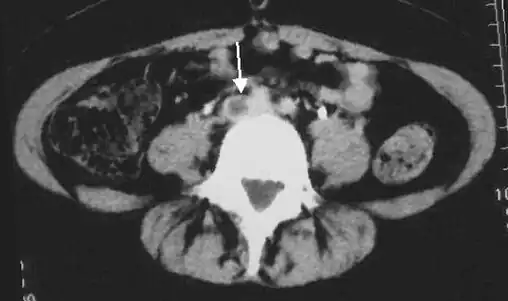

An abdominal CT scan demonstrating an iliofemoral DVT, with the clot in the right common iliac vein of the pelvis

-